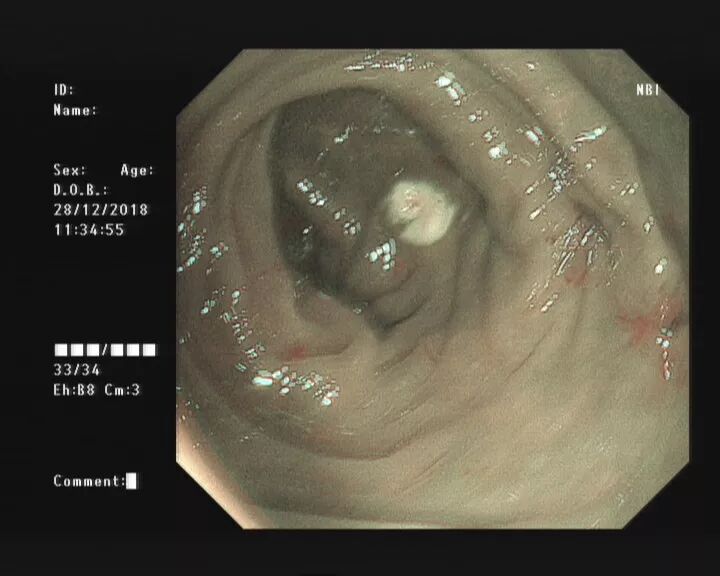

(下图可见白色脓液)

当黄斑马导丝及导管置入阑尾腔时,可见脓性分泌物涌出。

随之进行阑尾腔冲洗;